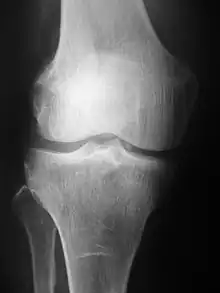

Radiography of the knee using a DR machine

Radiographs (originally called roentgenographs, named after the discoverer of X-rays, Wilhelm Conrad Röntgen) are produced by transmitting X-rays through a patient. The X-rays are projected through the body onto a detector; an image is formed based on which rays pass through (and are detected) versus those that are absorbed or scattered in the patient (and thus are not detected). Röntgen discovered X-rays on November 8, 1895, and received the first Nobel Prize in Physics for his discovery in 1901.

In film-screen radiography, an X-ray tube generates a beam of X-rays, which is aimed at the patient. The X-rays that pass through the patient are filtered through a device called a grid or X-ray filter, to reduce scatter, and strike an undeveloped film, which is held tightly to a screen of light-emitting phosphors in a light-tight cassette. The film is then developed chemically and an image appears on the film. Film-screen radiography is being replaced by phosphor plate radiography but more recently by digital radiography (DR) and the EOS imaging.[5] In the two latest systems, the X-rays strike sensors that converts the signals generated into digital information, which is transmitted and converted into an image displayed on a computer screen. In digital radiography the sensors shape a plate, but in the EOS system, which is a slot-scanning system, a linear sensor vertically scans the patient.

Plain radiography was the only imaging modality available during the first 50 years of radiology. Due to its availability, speed, and lower costs compared to other modalities, radiography is often the first-line test of choice in radiologic diagnosis. Also despite the large amount of data in CT scans, MR scans and other digital-based imaging, there are many disease entities in which the classic diagnosis is obtained by plain radiographs. Examples include various types of arthritis and pneumonia, bone tumors (especially benign bone tumors), fractures, congenital skeletal anomalies, and certain kidney stones.